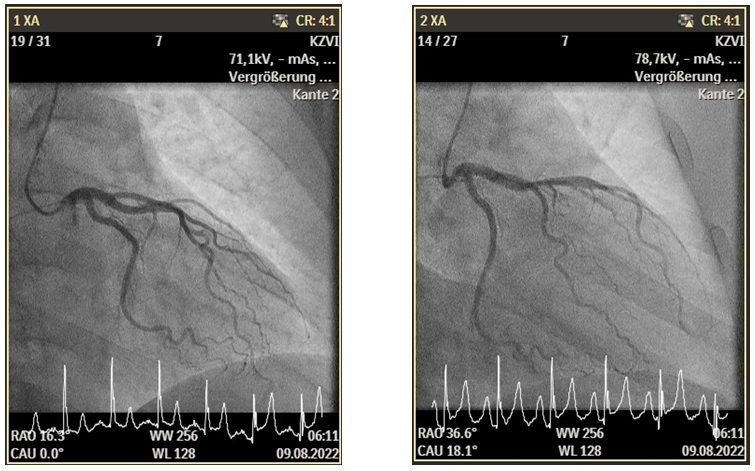

A 47-year-old female presented to our Emergency Department (ED) because of typical chest pain, the patient has never this pain, at admission day was the first time. This patient has no previous history of DM or hypertension. An electrocardiogram was performed, which showed sinus rhythm with ST elevation in II, III, and AVF. This Patient has a hs-TNI at 7ng/dl at hour 0 (normal 2.3-11.6 ng/l), 4 hours after the admission was hs-TNI at 600 ng/dl. The coronary angiogram was without a significant epicardial coronary artery disease. For further evaluation, we measured the microcirculatory resistance (IMR=15) and coronary flow reverse (CFR =3,7) which were not pathologic (Figure 1).

Figure 1. TEE Bilder.